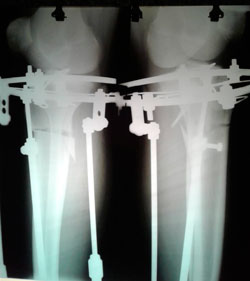

на фиксации

image-28-08-20-01-09-4.jpg

image-28-08-20-01-09-3.jpg